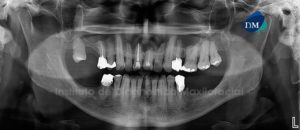

Paciente masculino de 61 años acude al Instituto de Diagnostico Maxilofacial para evaluación general de las piezas dentarias. A la evaluación panorámica se aprecia a